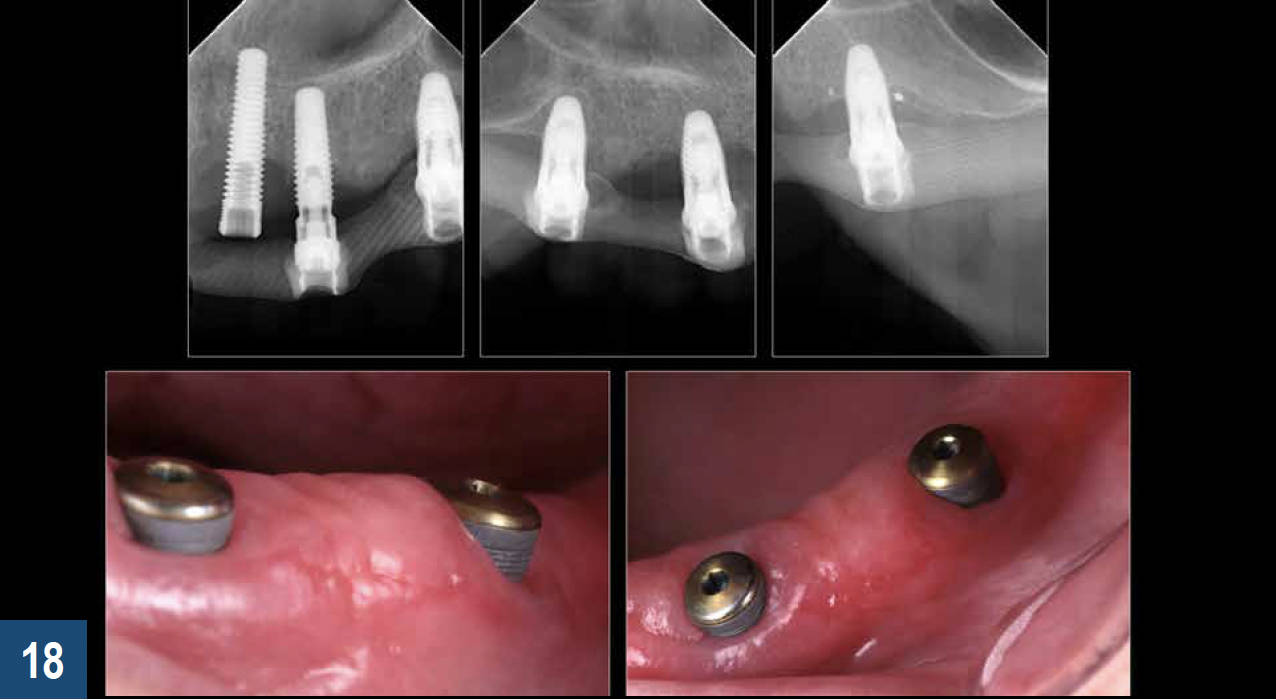

PERIODONTICS

Early intervention in the management of oral biofilms is critical to avoid the breakdown of the surrounding hard and soft tissue in patients with dental implants. It is not uncommon for patients to present to the clinic with implant-supported prosthetics that are in the advanced stages of failure (Figure 16). Often these individuals experience no discomfort or functional issues, and they are not ready to have their implants removed. For the edentulous patient in this situation, the overdenture may serve as a convenient vehicle to deliver an application of 10% carbamide peroxide to the implant threads (Figure 17). Carbamide peroxide in a concentration of 10% possesses a bacterial inhibitory effect on both Streptococcus mutans and Lactobacilli when applied for 2 hours or more,44and the hydrogen that is released has been further shown to efficiently suppress the growth of Actinomyces actinomycetemcomitans.45 Although not clinically ideal, leveraging the antibacterial effects of 10% carbamide peroxide to aid in the reduction of bioburden and oral pathology around failing implants (Figure 18) may serve to provide the patient with the protracted time necessary to prepare mentally and financially for the transition towards a new prosthesis and oral situation.

Fig 18. Top panel: Vertical bone loss around endosseous implants may result in loss of soft tissue and exposed implant threads that are challenging to keep clean because of their roughened surface. Bottom panel: Application of 10% carbamide peroxide using a custom-fit tray (Pola Night, SDI) or the patient’s existing removable prosthesis aids in the maintenance of a clean implant surface through the reduction of bioburden and build-up around the exposed titanium threads.v